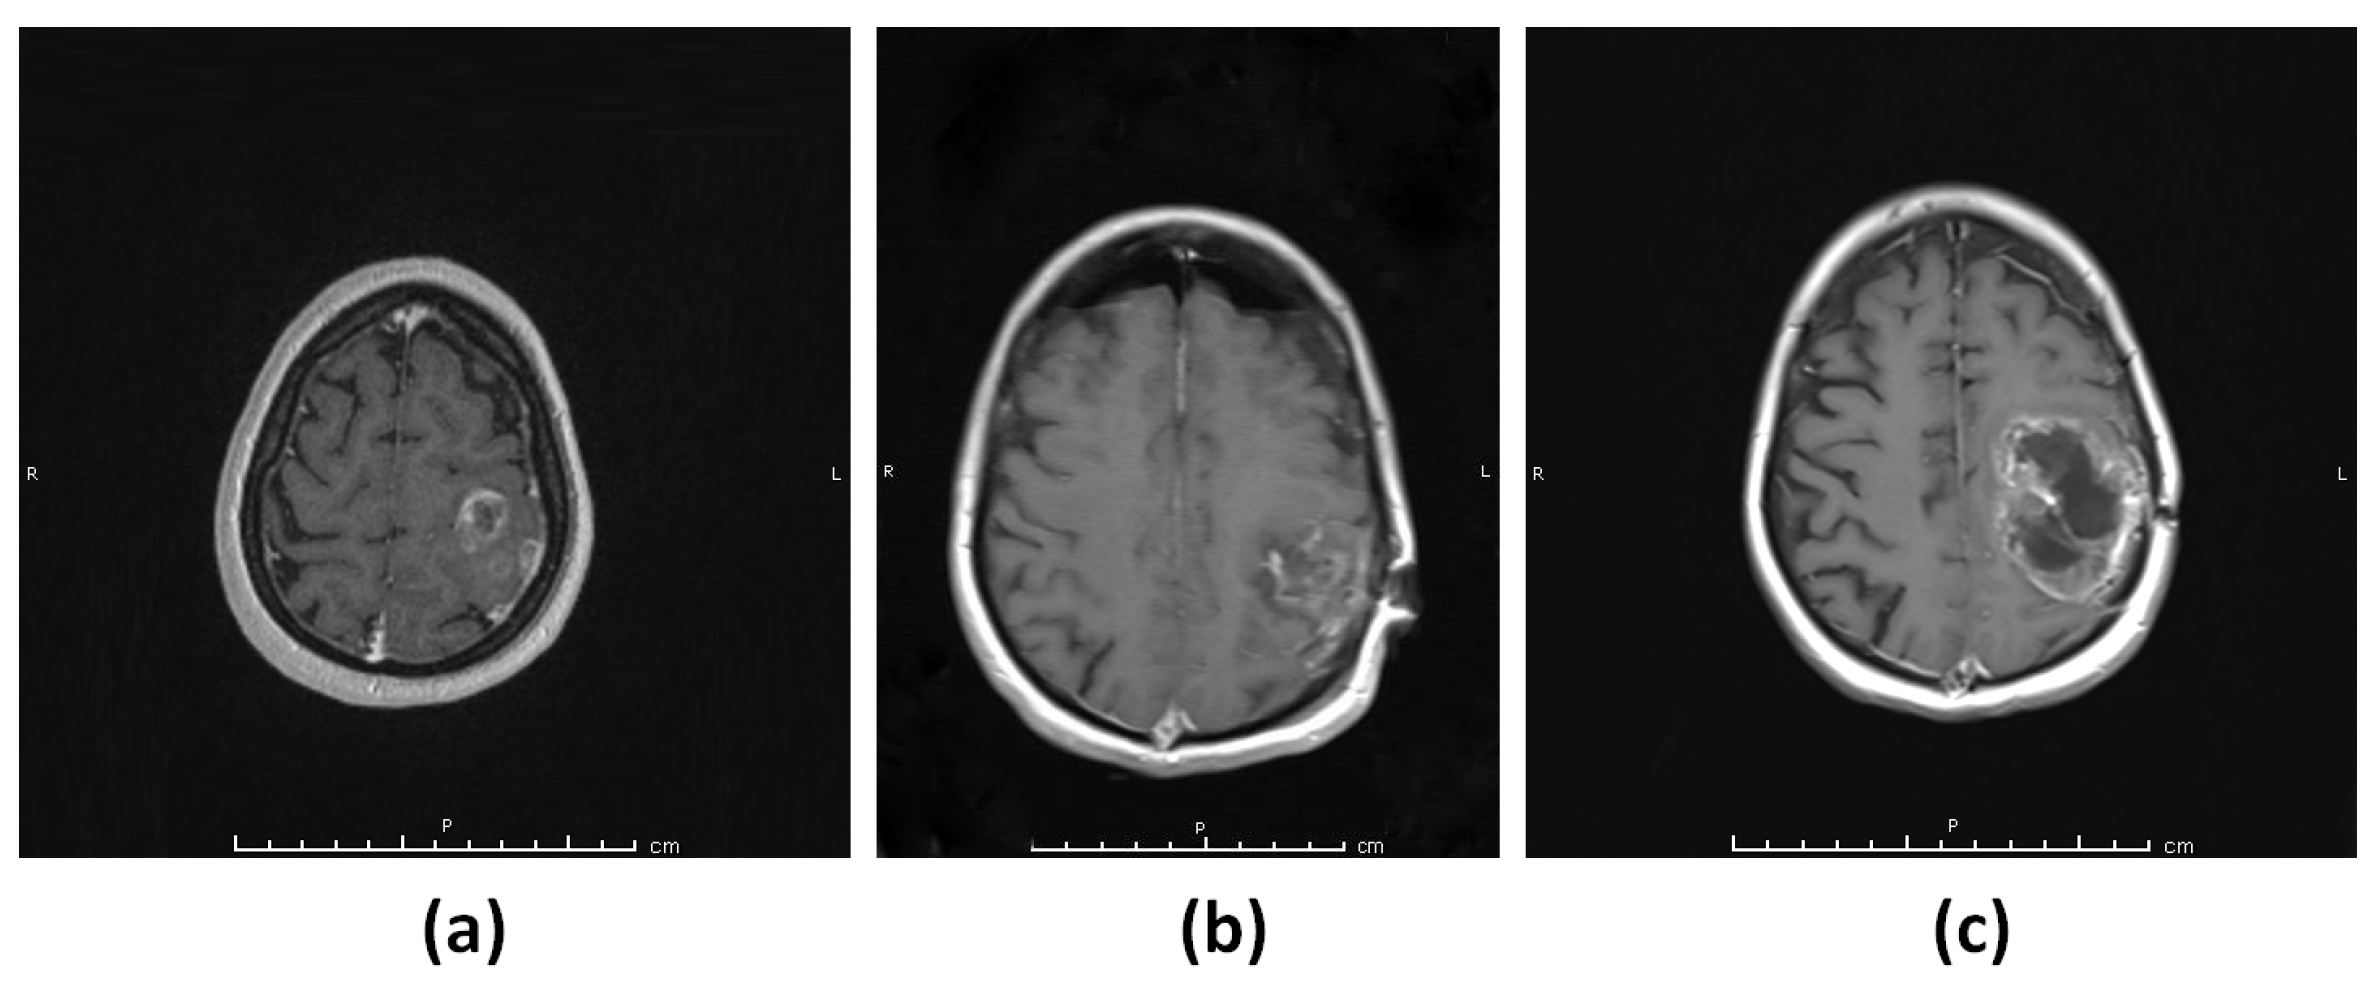

3.1.2. Patient 2 (G2)

3.1.3. Patient 3 (G3–4)

3.1.4. Patient 4 (G5)